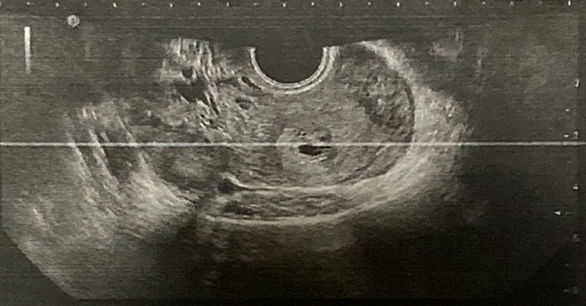

血液検査で23日(土)に排卵していたことがわかって 移植が28日(木)に決定❣️ AAの1番良いグレードの受精卵から移植することに!移植の際に受精卵が着床しやすくするために 切れ込みを入れてもいいか確認された 凍結してある受精卵は透明帯という膜が硬くなるため切れ込みを 入れたほうが受精しやすくなるそう❣️ アシステッドハッチングって方法らしい 移植に向けて2つの薬が処方された〜 エストラジオール錠 0.5mg (朝昼夕 食後に1錠 12日分) 卵胞ホルモンを補い子宮内膜を増殖させるウトロゲスタン膣用カプセル(1日2回 12時間ごとに膣奥に入れる) 黄体ホルモンを補い着床の促進、妊娠を維持する働…